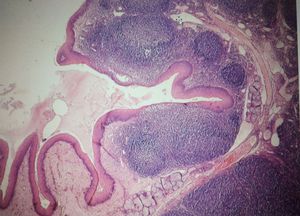

Guess !! what is this !?

Palatine tonsil

Yeh.it's lymphoid tissue, but it's a tonsile

It looks like peyers patch... so might be ileum

Surface epithelium bro see

Ileum has tall columnar epithelium